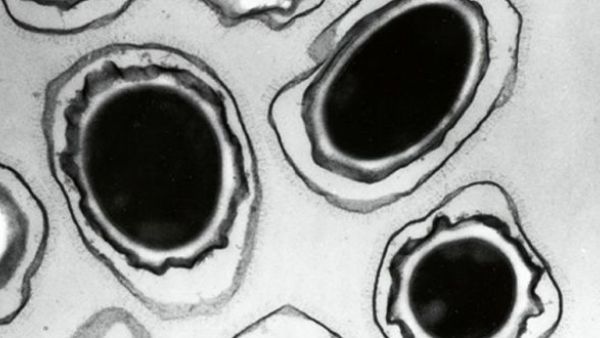

A microscopic view of anthrax spores. Photograph (AFP)